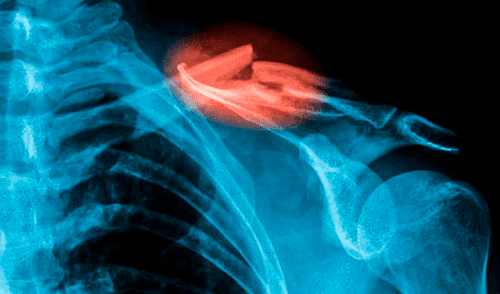

Investigadores desarrollaron una innovadora pistola de pegamento capaz de imprimir en 3D un material similar al hueso, ofreciendo una solución prometedora para la reparación de fracturas durante las cirugías. Modificando un dispositivo estándar, esta tecnología permite aplicar el material directamente sobre las fracturas, lo que podría transformar los procedimientos quirúrgicos.

Las primeras pruebas, realizadas en conejos, demostraron su efectividad, especialmente en fracturas irregulares, donde los métodos convencionales resultan más complejos de aplicar. Con su potencial para mejorar la precisión y la eficacia de las reparaciones óseas, esta pistola de pegamento 3D podría cambiar el futuro de la medicina quirúrgica.

Gracias a esta innovadora técnica, los investigadores lograron imprimir injertos óseos directamente sobre fracturas y defectos óseos durante intervenciones quirúrgicas en conejos. Este avance, como destacó el coautor del estudio, Jung Seung Lee, no solo acelera el tiempo de operación, sino que también aumenta la eficiencia en condiciones quirúrgicas reales.

En un experimento realizado con conejos blancos de Nueva Zelanda, los investigadores evaluaron la efectividad de los injertos óseos impresos en 3D al compararlos con el tratamiento tradicional con cemento óseo. Tras reforzar las fracturas con placas metálicas y tornillos, rellenaron los defectos óseos de los conejos con su filamento especial o con el cemento convencional, y luego monitorearon la evolución de los animales durante 12 semanas.

Los resultados mostraron que los conejos tratados con el injerto óseo impreso en 3D experimentaron una mejor regeneración ósea, con un tejido más denso y una formación ósea más robusta en comparación con los que recibieron el tratamiento tradicional. Al finalizar el estudio, el material experimental mostró una degradación de solo un 10%.